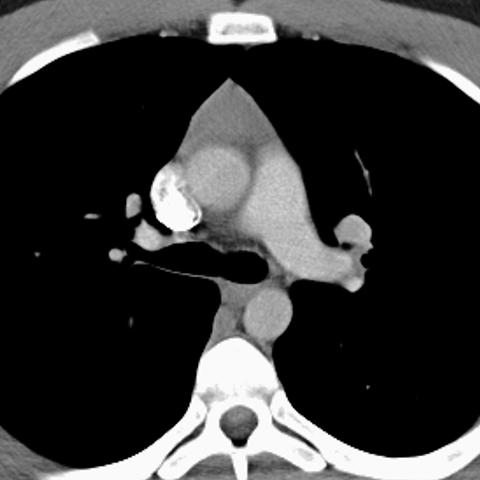

Normal Thymus, 15 Year Old (Chest CT) [1 of 3]